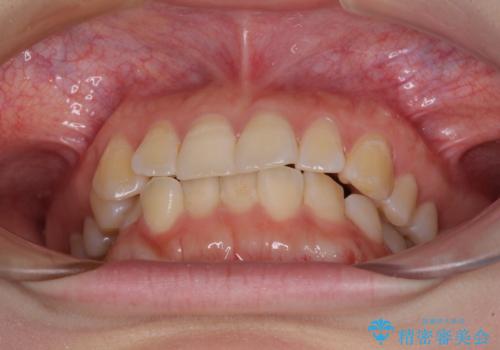

- 上下前歯のデコボコを気にして来院された患者様です。

ワイヤー矯正でもインビザライン矯正でも対応可能でしたが、インビザラインでの自己管理の煩わしさを避けるため、ワイヤー装置にて矯正治療を行うこととしました。

下顎前歯が1歯欠損しているため、上下正中は合わず、左右奥歯の咬み合わせは理想的とはならない仕上がりとなります。